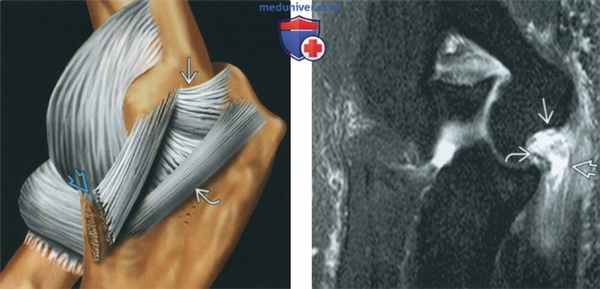

(Слева) Рисунок, латеральная поверхность локтевого сустава: показан разрыв переднею пучка локтевой коллатеральной связки (ЛоКС). Задний и поперечный пучки не изменены. Характерным для разрыва ЛоКС является повреждение переднею пучка, но может наблюдаться повреждение еще и заднего пучка.

(Справа) МР-артрография в режиме Т2ВИ FS, коронарный срез: отмечается отрыв переднею пучка ЛоКС с ретракцией культи в дистальном направлении. Также наблюдается поверхностный разрыв сухожилий сгибателей.